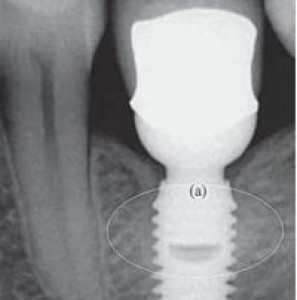

Il platform switching riduce almeno di 1/3 la perdita di osso intorno agli impianti e conferma gli effetti positivi già segnalati in letteratura. Questa in sintesi la conclusione di uno studio...

Uno dei criteri con cui si valuta la possibilità di realizzare un impianto dentale è il timore che nel tempo esso possa “consumare” la struttura ossea esistente e modificare i tessuti gengivali...